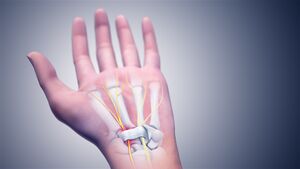

In the human body, the carpal tunnel or carpal canal is the passageway on the palmar side of the wrist that connects the forearm to the hand.[1]

The tunnel is bounded by the bones of the wrist and flexor retinaculum from connective tissue. Normally several tendons from the flexor group of forearm muscles and the median nerve pass through it. There are described cases of variable median artery occurrence.

When any of the nine long flexor tendons passing through the narrow carpal canal swell or degenerate, the narrowing of the canal may result in the median nerve becoming entrapped or compressed, a common medical condition known as carpal tunnel syndrome (CTS).[2][3]